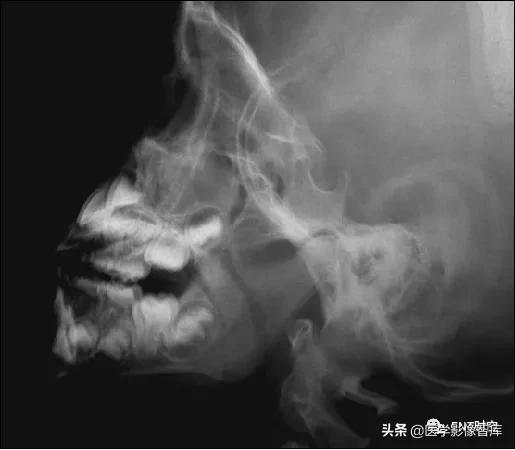

鼻咽后气道宽度(PAS)

软腭表面与腺样体表面最凸点之间有效气道宽度

作为PAS宽度 (图中a’),是鼻咽最小气道宽度

PAS宽度参考值:

- >10mm 属正常范围

- 6~10mm 腺样体生理性或中度肥大

- ≤5mm 腺样体重度肥大

- PAS≤3mm 患儿多有张口呼吸

- 有文献报道认为当A/N值≥0.71,PAS≤3mm可作为手术指征。